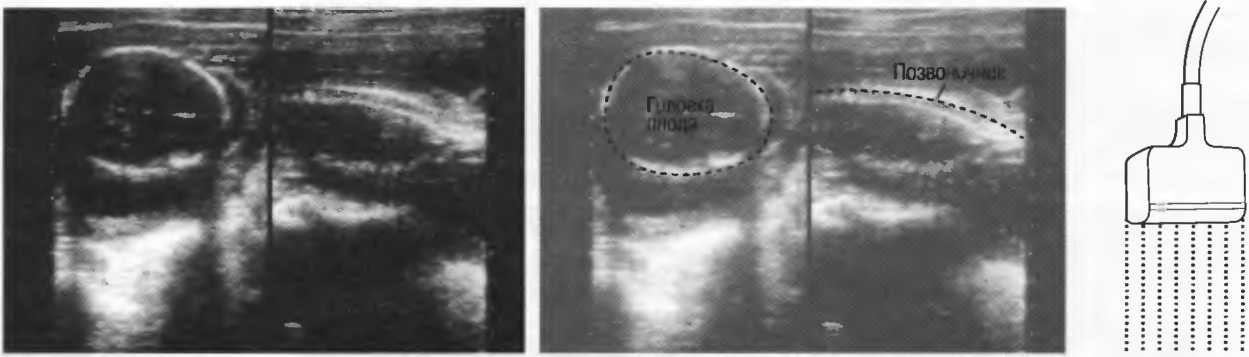

Кости скелета очень интенсивно отражают ультразвук, поэтому внутренняя структура кости либо другой сильно кальцинированной структуры не видна. В результате этого получение изображения через кости черепа или другие кости у взрослых невозможно (рис. 5).

Рис.5. Два поперечных среза плода, демонстрирующих тень от позвоночника плода. Аналогичная тень от ребер может частично закрывать почки или печень. Изменяя угол наклона датчика, можно изменить положение тени таким образом, чтобы подлежащие ткани были видны отчетливо.

1. Линейный датчик. Срезы при использовании таких датчиков имеют форму прямоугольников. Эти датчики наиболее удобны в акушерских исследованиях, а также при исследовании щитовидной и молочных желез (рис. 7а).

Рис.7а. Срезы прямоугольной формы, получаемые при использовании линейного датчика.